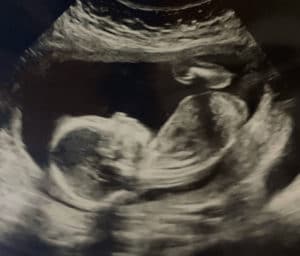

Mom Age 41 Is 20 Weeks Pregnant After Reversing Burned Tubal Ligation

20 Weeks And Counting!

We are currently measuring in a 20 weeks with a little girl and she is perfect.

I honestly didn’t go in with much hope because of my age (41) and we were completely shocked it took less than 4 months to get pregnant.

We are so grateful to you! Thanks will never be enough!

Patient age: 41

Tubal ligation type: Coagulation (burned)

Patient hometown: Tallahassee, Florida